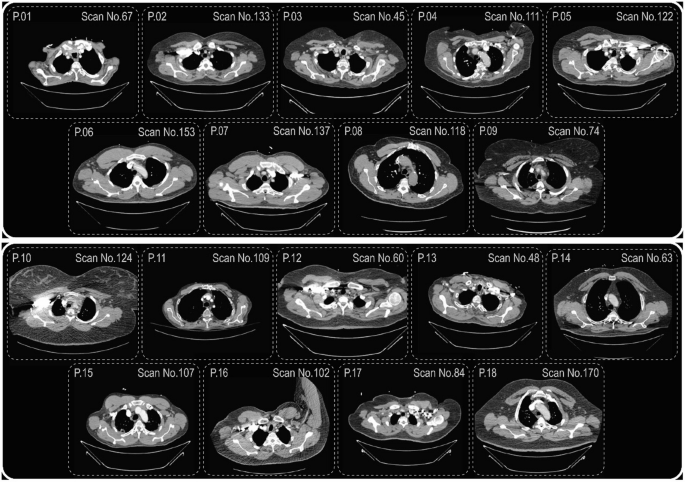

In this research, the selected optimization algorithms for medical image segmentation have been evaluated based on the TCIA dataset35. To assess the efficiency of the proposed approach, an imaging dataset publicly available from the Cancer Imaging Archive35 was utilized. This dataset includes CT images with a resolution of 762 × 762 pixels, pixel spacing of 1.08 × 1.08 mm and 0.98 × 0.98 mm, and a slice thickness of 3.14 mm. The images feature chest scans with clinical information for a rural COVID-19-positive population (COVID-19-AR), covering approximately 105 patients. For this research, a subset of 18 patient records were randomly selected to test and evaluate the approach.

This figure presents a comparative analysis of threshold values obtained by various optimization algorithms when applied to the Otsu criterion for multilevel thresholding. Each algorithm was executed on all 18 randomly selected CT images illustrated in Fig. 2 (arranged top-to-bottom, right-to-left). The second column in the table shows the threshold level (nTh). The third column displays the most frequent threshold values (MFV) identified across 25 independent runs for each algorithm. The fourth column provides the Number of Occurrences (NOT), indicating how often those threshold values were observed. For comparison, the corresponding Otsu baseline threshold values are also listed. The close alignment between the optimized and Otsu values, with minimal or no deviation, highlights the reliability of the proposed approach. All optimization algorithms aim to maximize the between-class variance, in accordance with the Otsu criterion.

Randomly selected CT scan images from top-bottom, right to left represent scans of patients 1–18.